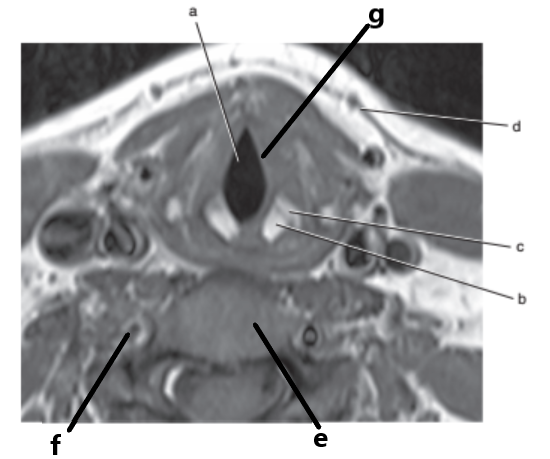

What is letter g ?

Vocal cords

What is letter f ?

Spinal cord

What is letter a ?

Glottis